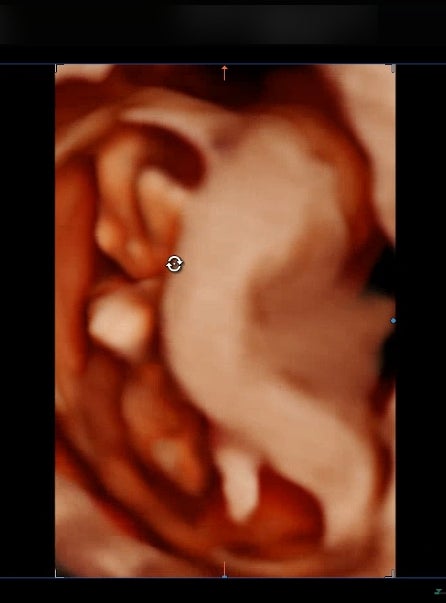

임신 12주 차 초코우유 먹고 1차 기형아 검사와 입체 초음파 하기 / 큐트루

안녕하세요 큐트루예요. 임신 12주 차 초코우유 먹고 1차 기형아 검사와 입체 초음파 하기 포스팅합니다. 1...